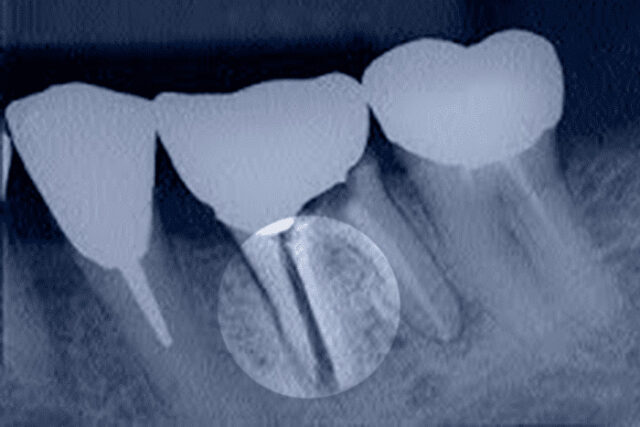

- при одномоментній імплантації, коли на місце пошкодженого зуба відразу встановлюють титановий гвинт;